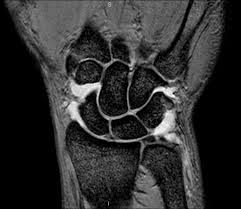

Dicho examen sirve para comprobar que el cartílago epifisario de la muñeca izquierda -que permanece abierto durante el crecimiento- no esté cerrado, ya que si lo está quiere decir que el jugador es mayor de 17 años.

El examen de muñeca fue impuesto por la Comisión Médica de la FIFA a partir de la edición de Nigeria 2009.